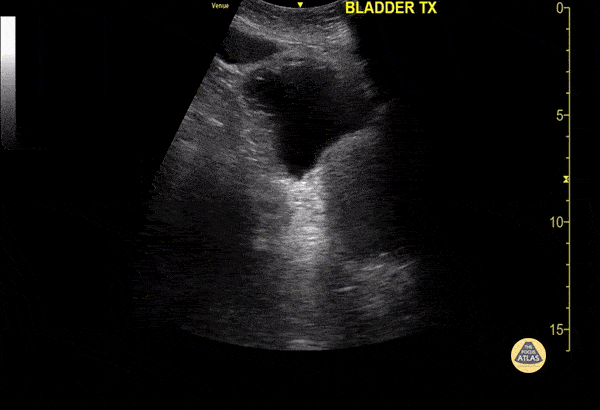

Renal/GU - Anterior Bladder Diverticulum

A 60 year old male presented to the emergency department for evaluation of hematuria. POCUS demonstrated a diverticulum extending from the anterior bladder surface. Mario Corro, MD, PGY-3, Staten Island University Hospital